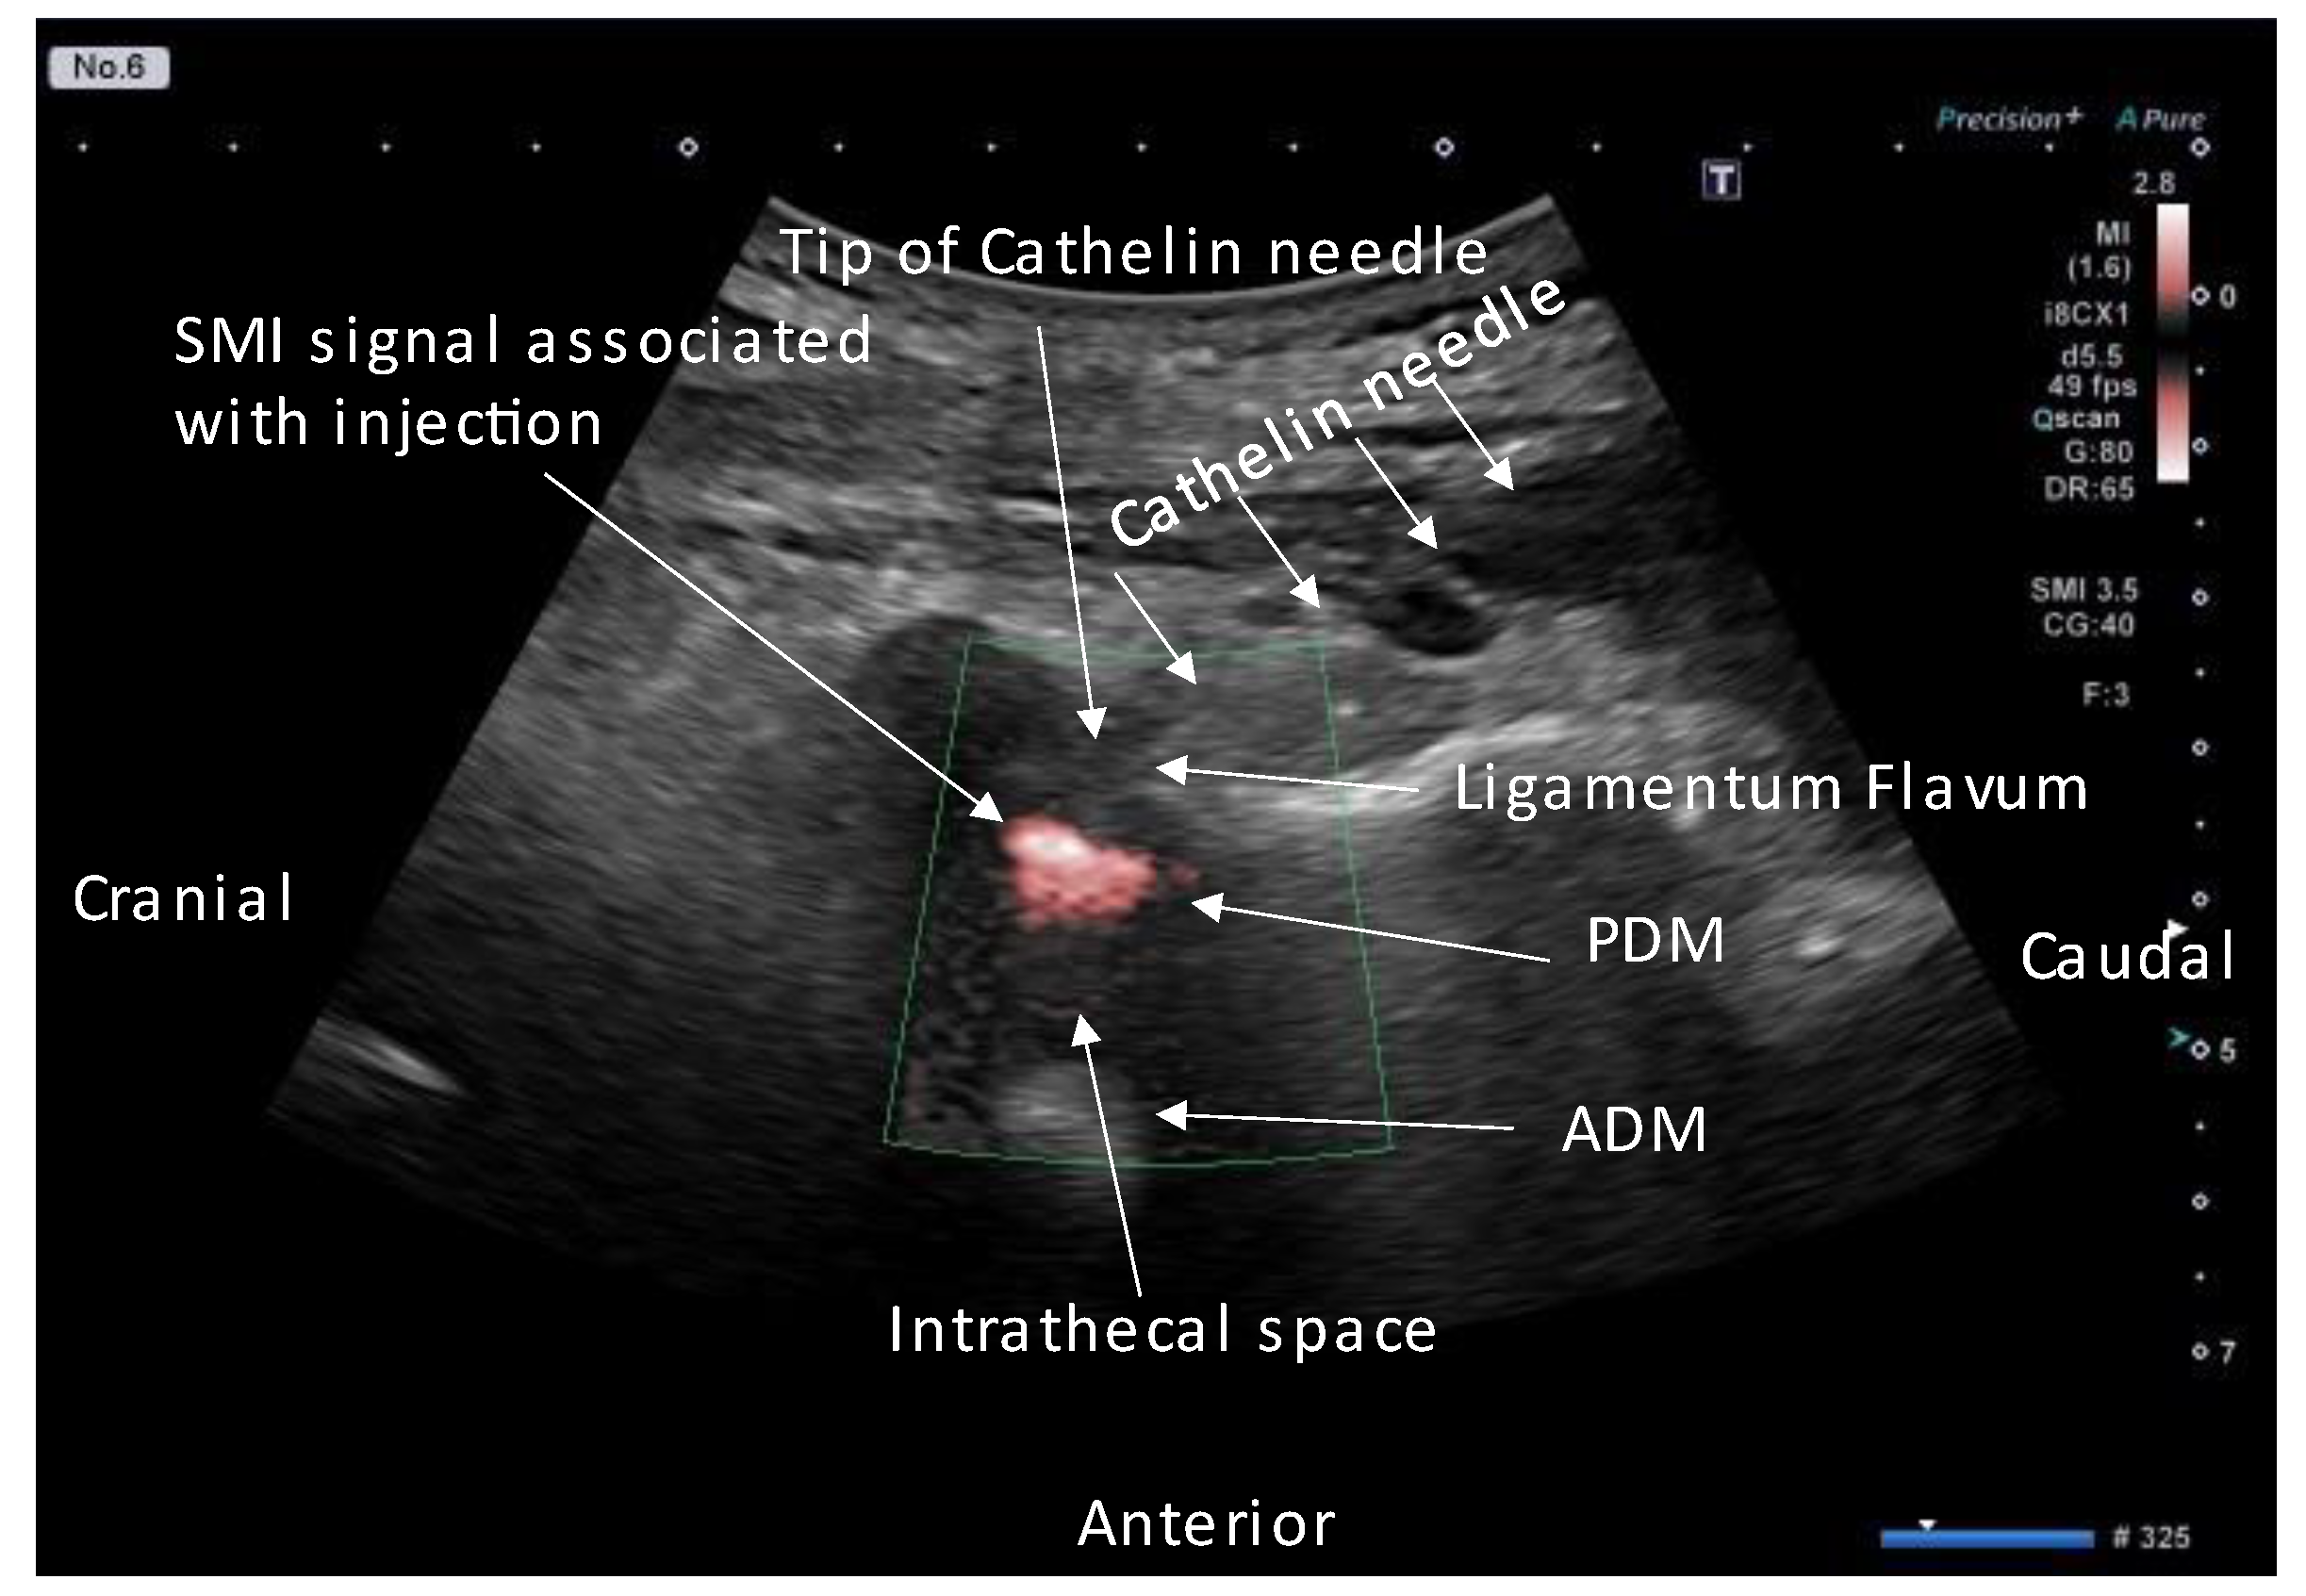

- Accurate needle tip guidance into the ligamentum flavum behind the epidural fat layer;

- Palpation of resistance by finger sense during ligamentum flavum insertion while confirming with sonography;

- Confirmation of the position of the needle tip in the ligamentum flavum;

- Tracing the spread of the drug in the epidural space using SMI during the injection.